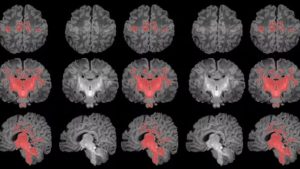

Os bebês passaram por ressonância magnética antes do primeiro mês de vida para avaliar o grau de maturação cerebral por meio dos níveis de mielinização.

Segundo os dados do estudo, houve uma correlação clara entre maior exposição materna a PM2.5 durante a gravidez e menor mielinização no cérebro dos recém-nascidos, tendo impacto no desenvolvimento infantil.

A exposição materna a partículas minúsculas no ar (PM2.5) está relacionada com uma mielinização mais lenta, indicando uma desaceleração da maturação cerebral. É importante destacar que tanto a desaceleração quanto a aceleração excessiva da maturação cerebral podem ser prejudiciais ao desenvolvimento infantil.